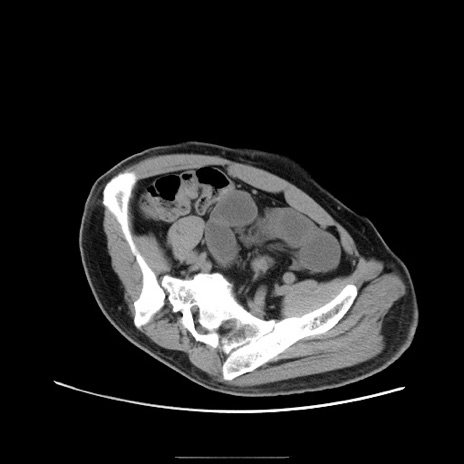

症例22(横断像)

【症例】50歳代男性

【主訴】腹痛

【現病歴】AVMからの被殻出血のため回復期リハ病棟入院中。 本日午後3時頃急に下腹部痛が出現した。

【既往歴】AVM、被殻出血、虫垂炎、高血圧

【身体所見】意識晴明、左半身不全麻痺、会話の理解は良好、36.5°C、腹部:膨隆、全体に板状硬、下腹部正中に圧痛点あり、反跳痛-、筋性防御不明、右下腹部にope scar

【データ】WBC 9400、CRP 0.06